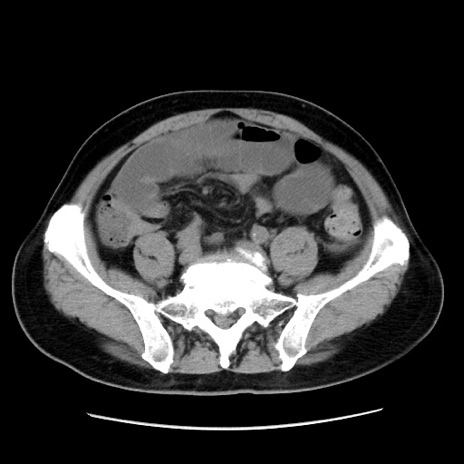

症例16(横断像)

【症例】 70歳代男性

【主訴】 腹痛、嘔吐

【現病歴】 約1ヶ月前より間欠的に腹痛と嘔吐あり、当院消化器内科を受診したところCTで多発する肝臓のLDAを指摘され、精査中であった。以降は消化器症状は安定していたが、2日前より嘔気と腹痛があり、同日より排便・排ガスが消失した。改善認めず、 本日、救急外来を受診した。

【既往歴】 大腸ポリープ切除後。

【身体所見】意識清明・会話良好、BT 36.3℃、BP 127/80mmHg、 P 80bpm、腹部:膨満あり、平坦・軟、上腹部正中および下腹部正中に圧痛あり、反跳痛なし、筋性防御なし。

【データ】WBC 7200、CRP 0.77